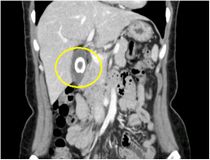

CT画像

造影CT冠状断像(胆嚢がん)